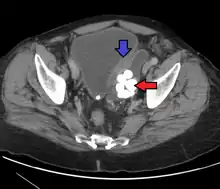

Urothelial carcinoma, previously called transitional cell carcinoma, is a type of cancer that can occur anywhere along the urinary tract.[7][8] This includes the kidneys, ureters, bladder, prostate, and urethra.[7][9] Symptoms may include blood in the urine, back pain, weight loss, or pain with urination.[1]

Risk factors include smoking, aromatic amines, arsenic, aristolochic acid, Schistosoma haematobium, and genetic disorders such as Lynch syndrome.[3][4][2] They develop from the transitional epithelium.[3] The diagnosis is generally confirmed by cystoscopy and biopsy.[5]

Transitional cell carcinomas are often multifocal, with 30–40% of patients having more than one tumor at diagnosis. The pattern of growth of transitional cell carcinomas can be papillary, sessile, or carcinoma in situ. The most common site of transitional cell carcinoma metastasis outside the pelvis is bone (35%); of these, 40 percent are in the spine.[14]